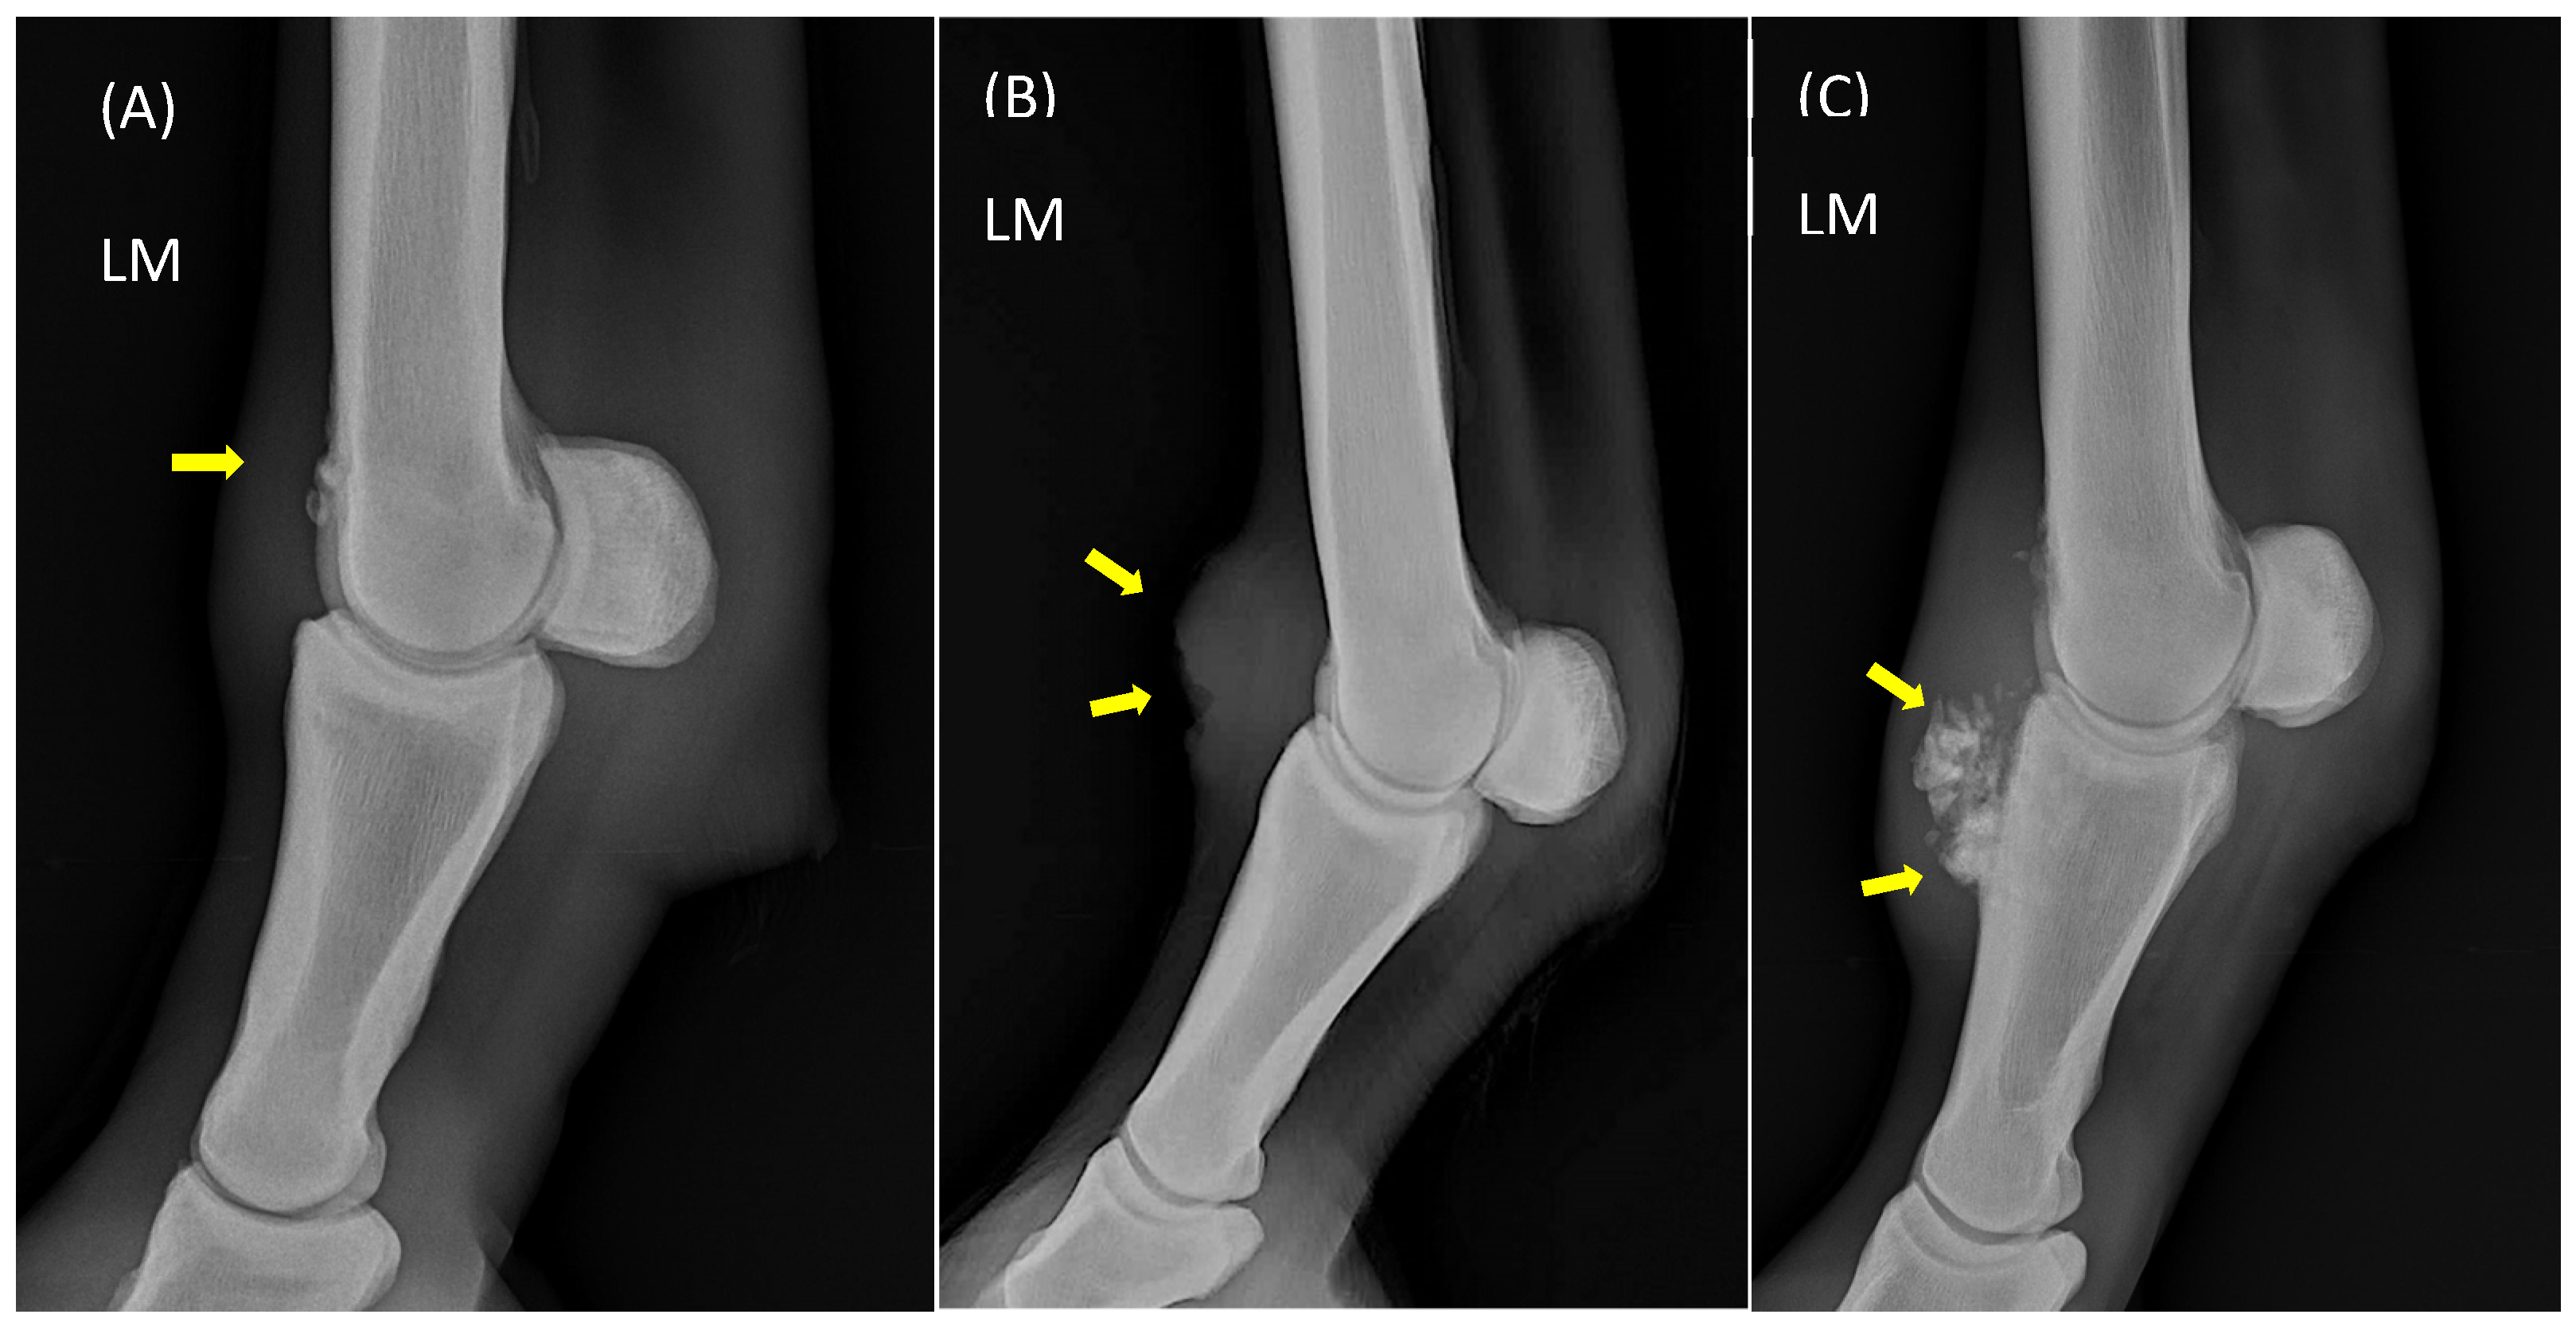

2.4. Radiographic Evaluation

3.3. Radiographic Scoring

4.2. Radiographic Findings